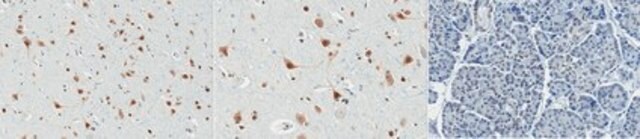

Immunohistochemistry (Paraffin) Analysis: A 1:250 and 1:50 dilution from a representative lot detected PQBP1 in human cerebral cortex and human pancreas tissue sections, respectively.